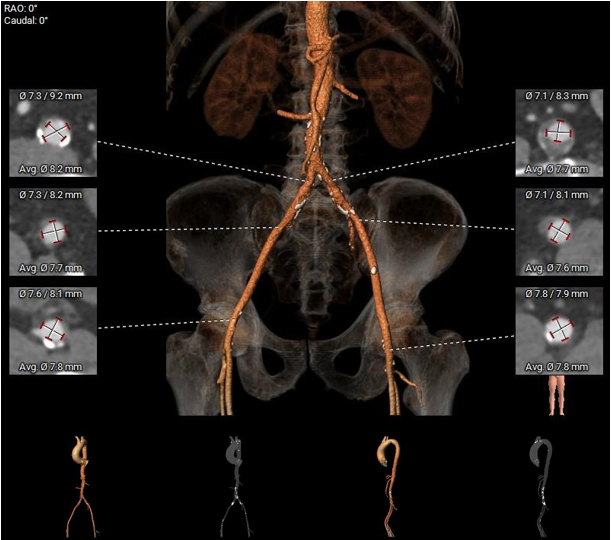

1.主动脉瓣瓣环周长90.6mm,平均周长径28.8mm。

2.主动脉瓣成三叶式,瓣叶明显增厚伴重度钙化,钙化均匀分布与三窦瓣叶上。

3.左右冠脉开口高度可。

4. 左室腔内径较大,心室壁厚度可,横位心,升主动脉扩张。

5.双侧股动脉入路血管管径良好。

主动脉根部评估

瓣环上解剖结构评估

外周血管及主动脉弓解剖

1. 考虑到患者瓣叶有增厚伴重度钙化,结合瓣环大小,downsize选择预装AV29瓣膜。

2. 考虑到患者升主动脉扩张,夹层、血管破裂等并发症风险提升,所以术中可能需要圈套器辅助过弓。

3. 根据术前CT评估,跨瓣角度为RAO 10° CAU 14°(右窦中心)左右,球囊预扩角度为为 RAO 6° CAU 6°(左冠切线位)左右,释放角度为释放角度 角度 RAO 25° CAU 35°(左右重合位)左右。使用23mm球囊预扩,充分利用沛嘉TaurusElite产品可回收的功能,瓣环上0mm高度释放,为高概率发生的瓣膜下滑留下缓冲位置。

4. 患者双侧入路血管条件佳,常规选择右侧股动脉为主入路,左侧为辅入路。